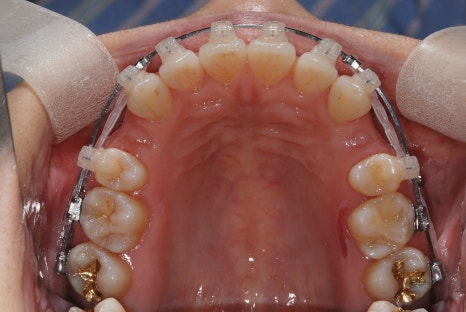

After a detailed analysis of the patient’s facial features, X-rays, and dental arches,

we expanded the shape of the upper and lower arches,

This is what it looks like while wearing the arch expansion device

and performed tooth extraction for backward movement of the lower jaw, moving the lower front teeth backward.

In this process, we also precisely adjusted the occlusion so that the temporomandibular joint would not be strained.